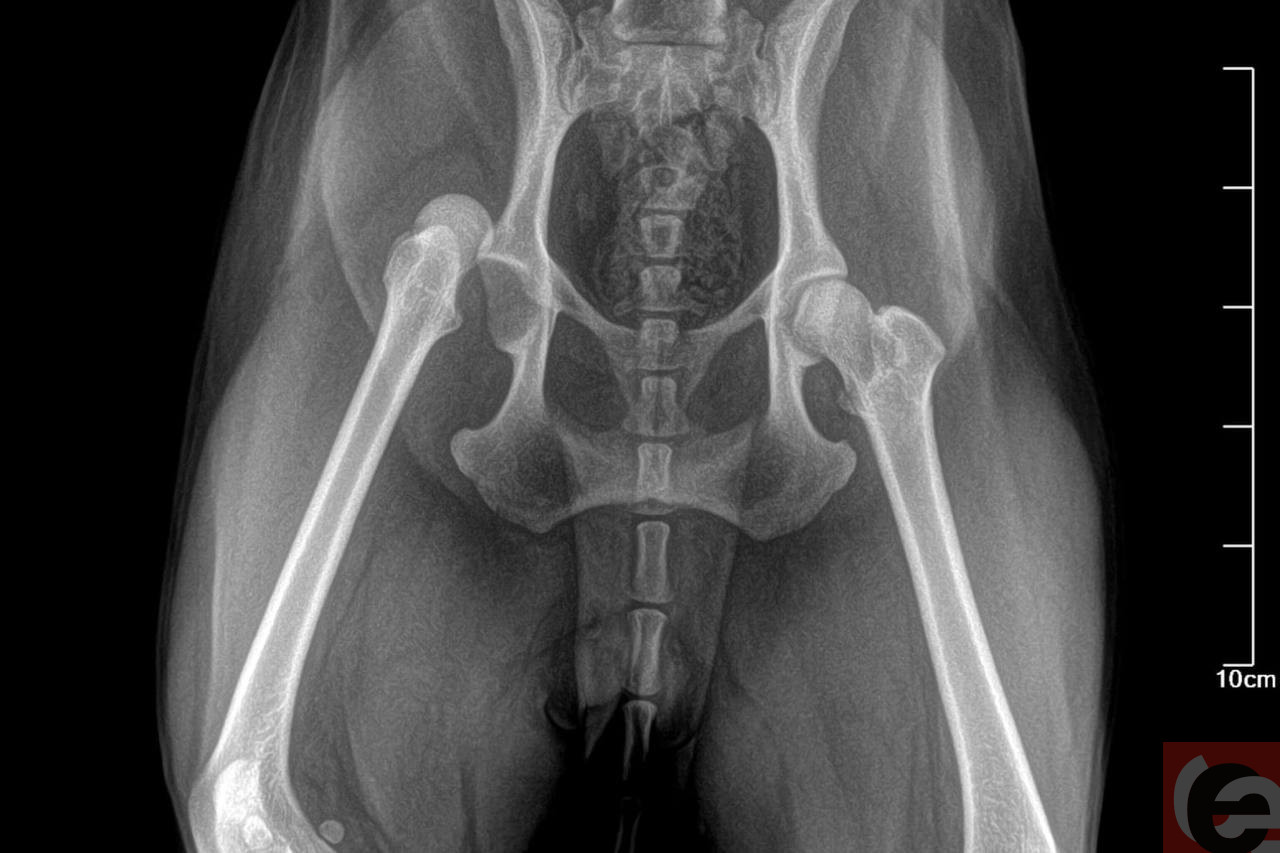

— В ветклинике мне сказали, что нарушилось кровообращение в лапе, поэтому Ника не может самостоятельно ходить. Хотя когда конечности «затекают», это быстро проходит. На следующий день я вновь повела Нику в клинику. Хирург сделал рентген и поставил диагноз — «вывих тазобедренного сустава», — поделилась обеспокоенная сибирячка.